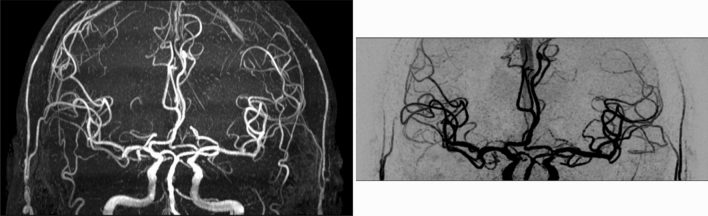

Figure 1.

Coronal maximum/minimum intensity projection of TOF (left) and SNAP (right), showing spatial coverage in the feet-head direction.

The main imaging parameters of the MR sequences were as follows. TOF: FOV 190 × 180 × 105 mm3, 6 slabs, voxel size 0.5 × 0.5 × 1 mm3, total acquisition time 6 min 37 s; SNAP: FOV 180 × 180 × 70 mm3, voxel size 0.8 mm isotropic, total acquisition time 3 min 45 s; ASL: using pseudo-continuous labeling scheme, FOV 240 × 240 × 125 mm3, voxel size 3 × 3 × 5 mm3, labeling duration 1800 ms, post labeling delay 2000 ms, total acquisition time 4 min 55 secs; PC: FOV 180 × 180 × 70 mm3, voxel size 0.5 × 0.5 × 1 mm3, encoding velocity 100 cm/s in all three directions, total acquisition time 5 min 4 s; iSNAP: FOV 204.8 × 179.2 × 144 mm3, voxel size 0.8 mm isotropic; 2D T2W FLAIR: FOV 230 × 230 mm2, in-plane resolution 1.28 × 1.28 mm2, slice thickness 4 mm, gap between slices 1 mm, 25 slices, total acquisition time 2 min. Note that the FOVs of the SNAP and 3D PC scans were purposely positioned upwards to cover more distal arteries, with the distance between circle of Willis and inferior edge of FOV being around 13 mm (Fig. 1)17. Other details of the protocols of TOF, SNAP, ASL and PC were described elsewhere17.